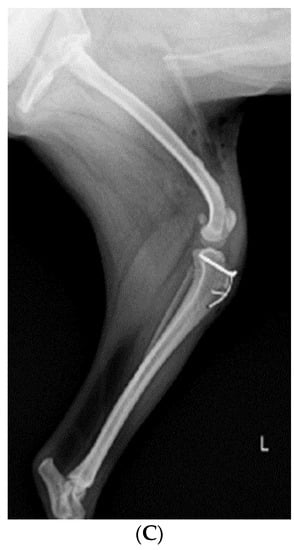

Before surgery, antibiotic and anti-inflammatory drugs were applied for about a month to relieve pain, edema, and arthritis; then, the surgery was performed. For treatment, amoxicillin/clavulanic acid (12.5 mg/kg, Amocla, KUHNIL corp., Seoul, Republic of Korea), carprofen (2.2 mg/kg, RIMADYL, Zoetis Inc., Parsippany-Troy Hills, NJ, USA), tramadol (2 mg/kg, Tridol cap. Yuhan Corp, Seoul, Republic of Korea), and famotidine (0.5 mg/kg, Famotidine, Hanmi Pharm, Seoul, Republic of Korea) were prescribed BID for 4 weeks. After one month, radiographic findings confirmed that inflammation and edema in both stifle joints were reduced (Figure 2). The owner was informed that stifle joint arthrodesis was to be performed on the right hind limb due to severe osteoarthritis, loss of the patella, and rupturing of the cranial cruciate ligament and that MPL correction was to be performed on the left leg. Accordingly, the consent of the guardian was obtained.

Figure 2.

Preoperative craniocaudal (A) and mediolateral (B,C) radiographs of the right and left stifle joints. The prescribed anti-inflammatory drugs reduced pain, lowered fever, and decreased inflammation (swelling and damage) after about a month. Arrows in images show areas with significantly reduced inflammation and edema compared to a month prior.